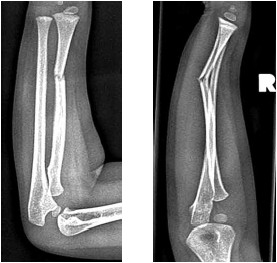

Criança de 4 anos de idade é atendida após queda de bicicleta com trauma em um dos braços. As radiografias anteroposteriores laterais são mostradas a seguir:

(Arquivo pessoal; imagem usada com autorização)

A principal hipótese diagnóstica é fratura